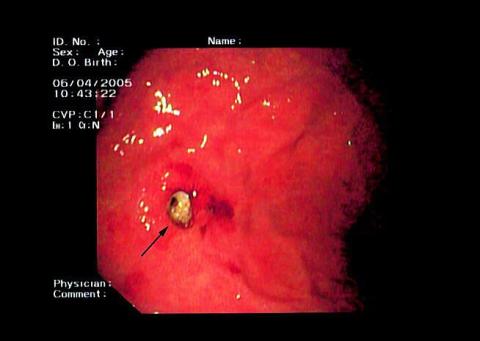

En patient, der blev overflyttet til en medicinsk gastroenterologisk afdeling, var hypotensiv, havde takykardi og tegn på øvre gastrointestinal blødning. Der var tidligere konstateret B-celle-lymfom i cardiaregionen. Patienten havde en perkutan endoskopisk gastrostomi (PEG)-sonde pga. tidligere hypofarynxcancer. Der blev aspireret ca. 500 ml frisk blod fra sonden. Der var ikke oplysninger om indtag af ulcerogen medicin. Ved en øsofagoduodenoskopi (ØGD) fandt man oversigtsforholdene vanskeliggjort pga. blod i ventriklen, og sikkert focus for blødningen kunne ikke identificeres. Efter stabilisering af tilstanden og gentagelse af ØGD fandt man pladen fra PEG-sonden næsten begravet i submucosa og let blødning fra området (se pil på billedet).

Konklusion: Det drejede sig om et tilfælde af buried bumper syndrome , som har medført kraftig akut blødning efter erosion af ventrikelvæggen. Buried bumper syndrome er et velbeskrevet fænomen [1], som kun sjældent giver anledning til så voldsom blødning. Syndromet er dog beskrevet med dødelig udgang i form af perforation og efterfølgende peritonitis [2].